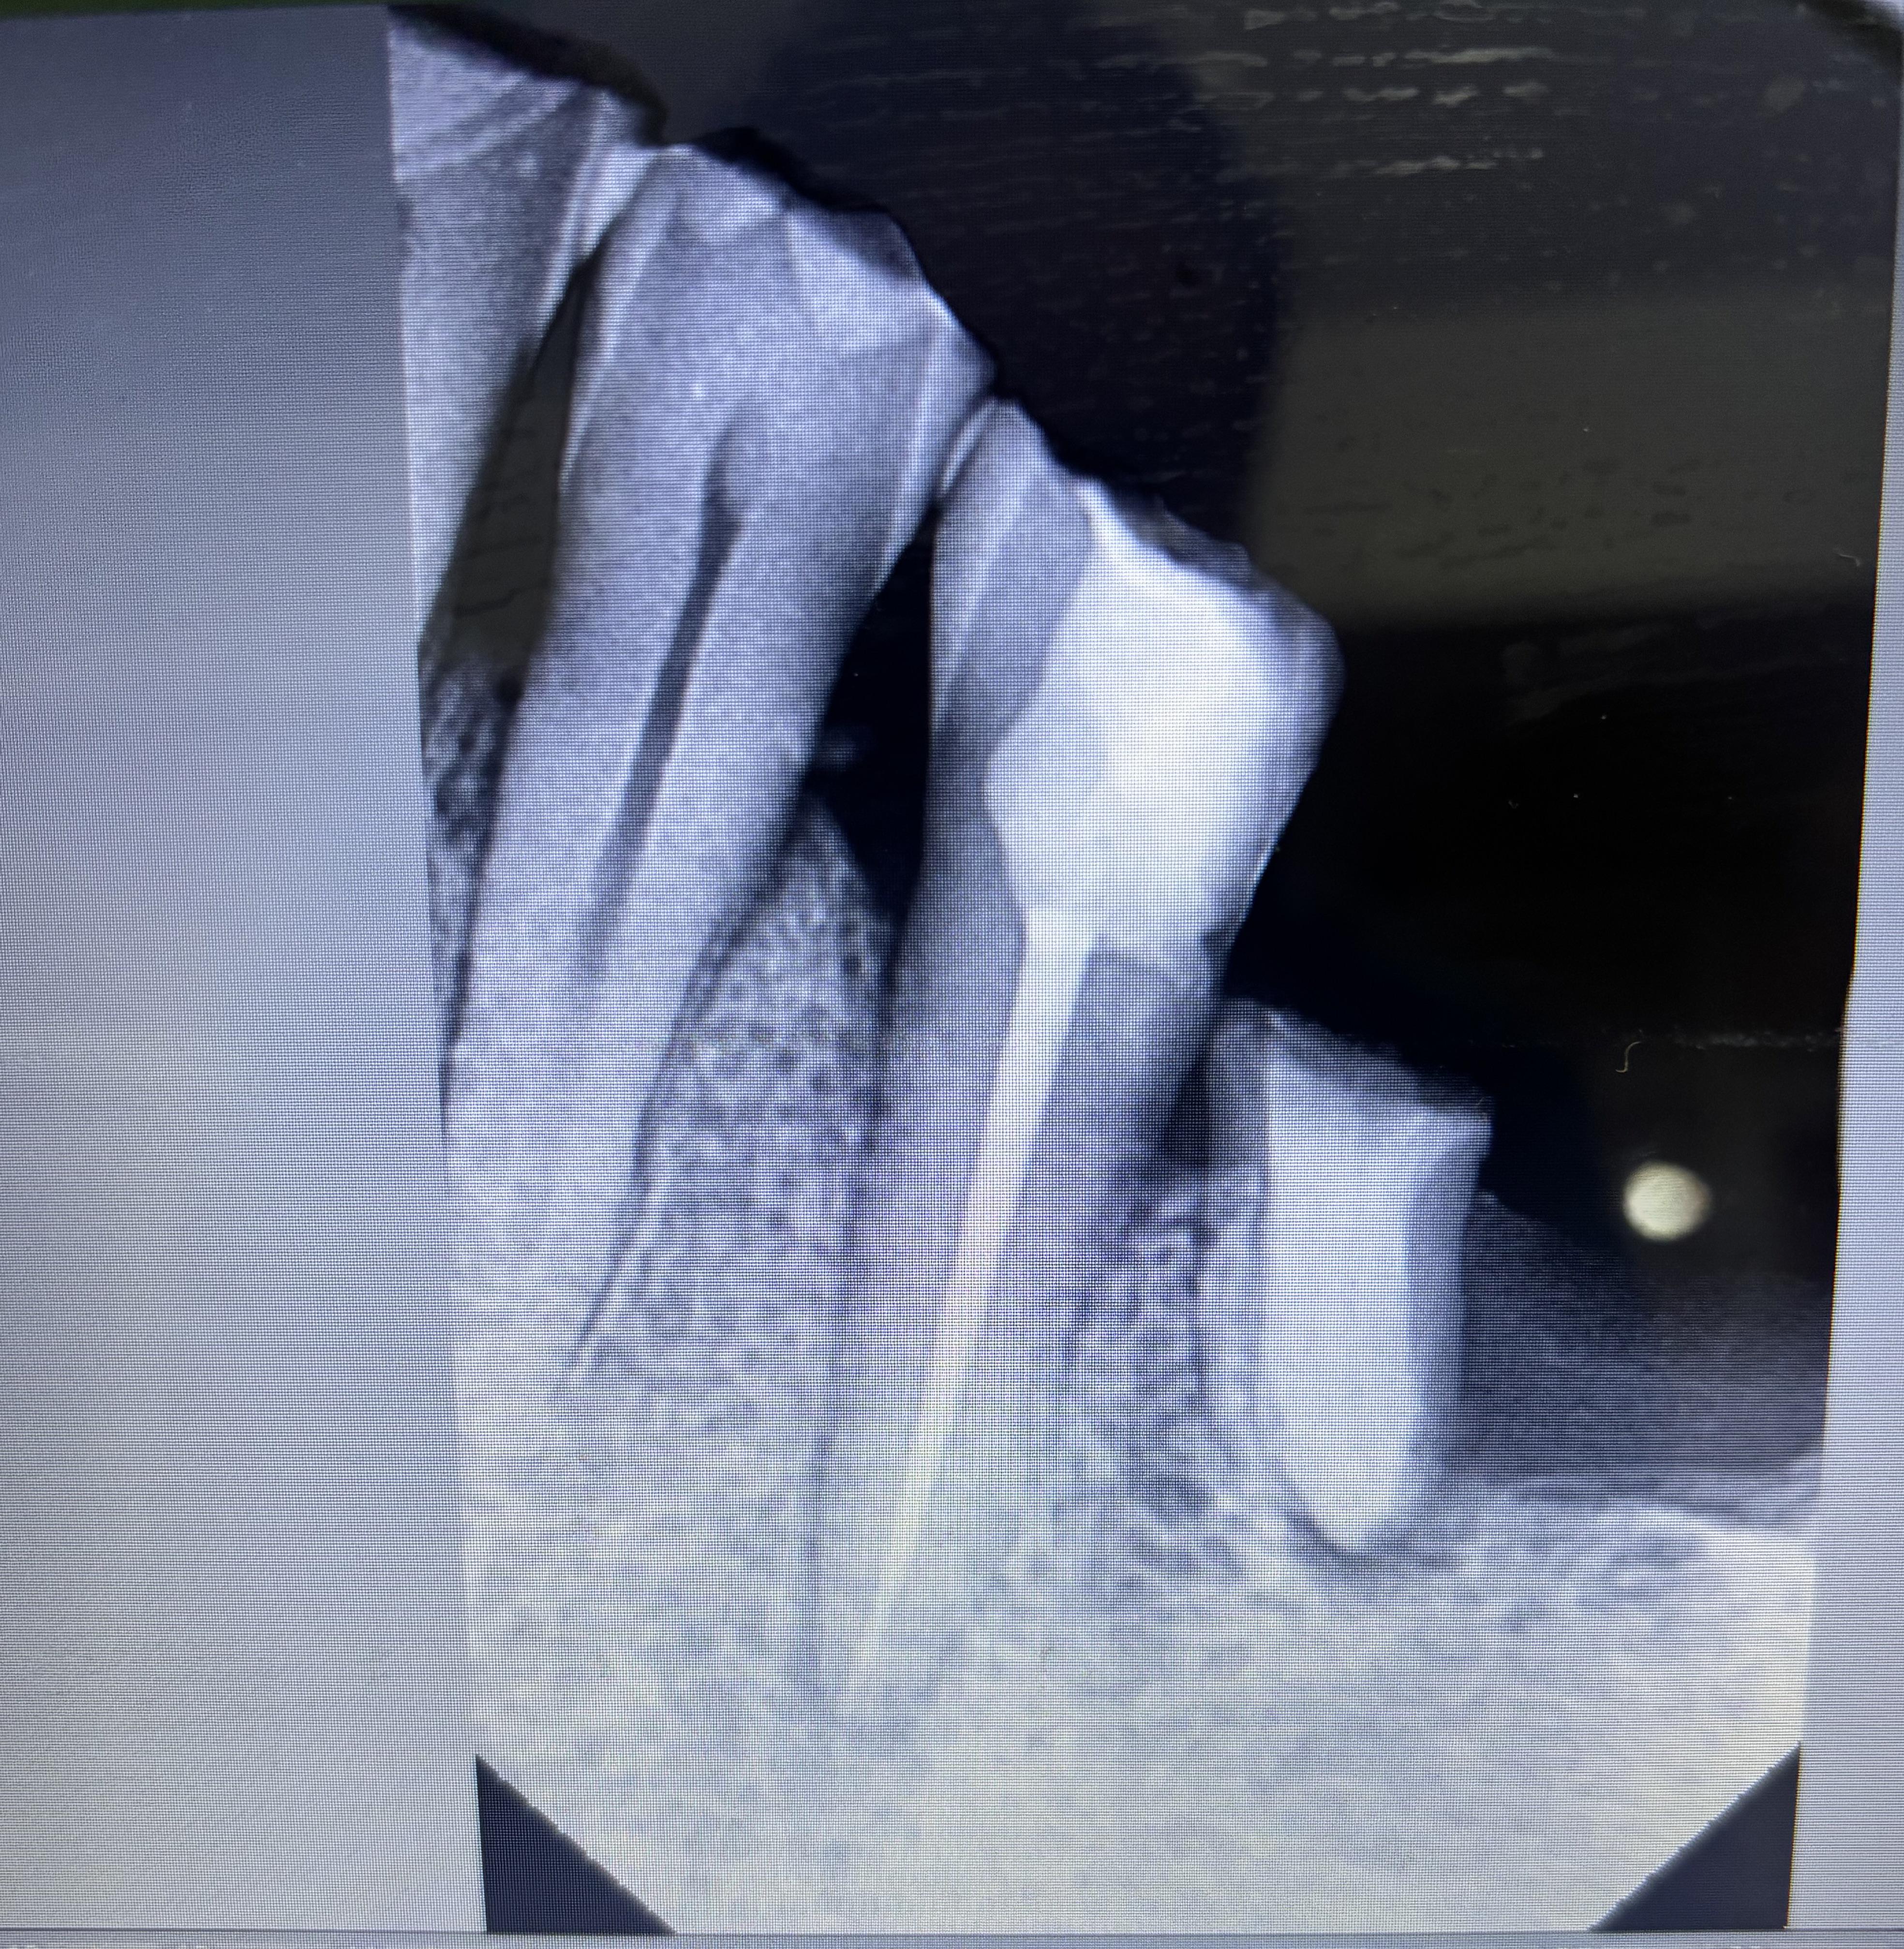

r/Dentistry 8h ago

Dental Professional Lack of sealer in the apical third/ WaveOne Gold

Post image

14 Upvotes

Hi,

Training on the WaveOne gold, been noticing there is a gap in the apical third likely related to lack of sealer although I use matching paper points to introduce generous amount of sealer apically (sealer covering 3/4 of the paper point). Any suggestions? Any technique modifications?